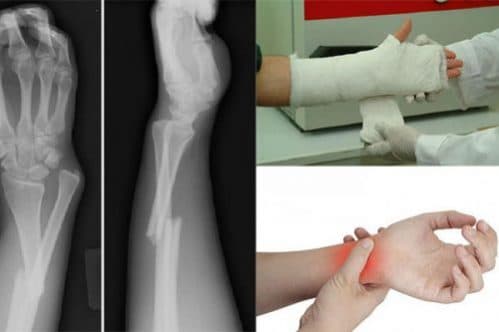

=> Đó là những dấu hiệu phổ biến nhất khi bị gãy xương. Tuy nhiên để chuẩn đoán tốt nhất về tình trạng kết quả có bị gãy xương thật hay không bạn nên đến cơ sở y tế để chụp X – Quang.

Đau đớn cực độ và sưng nhiều là biểu hiện khi bị gãy xương